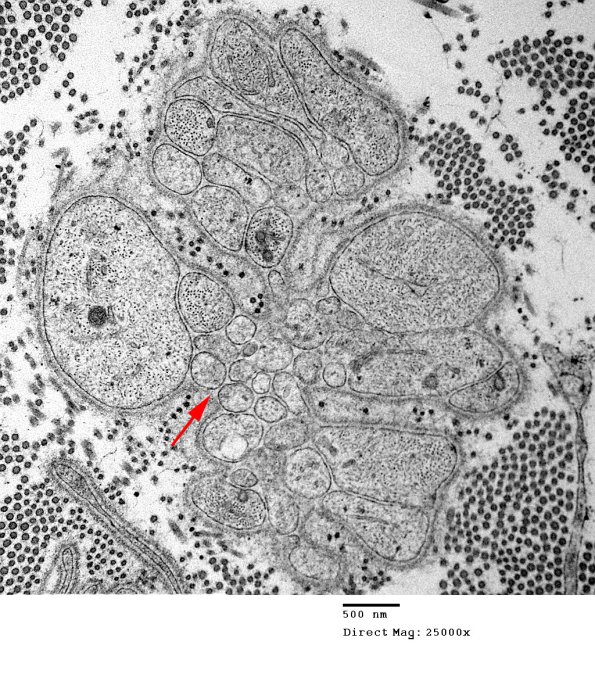

As myelin and axonal debris are removed, Schwann cells proliferate and send out numerous processes forming bands of Büngner, which represent conduits along which regenerative axons grow to try to reform their original connections. In many cases in which the profiles are small and round it is difficult to definitively separate Schwann cell processes from possible early regenerative axonal sprouts (arrow).